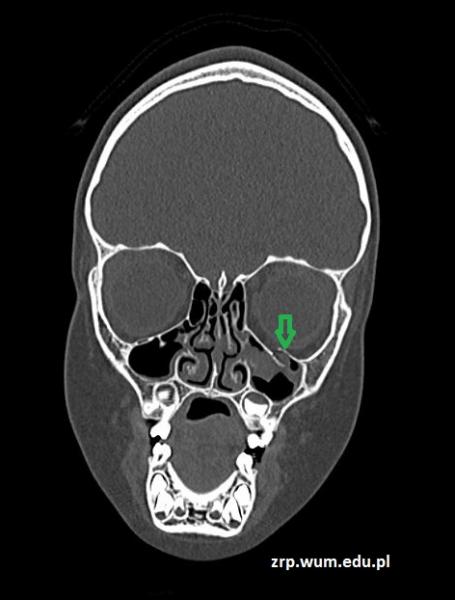

Przypadek 47: 5-letnia dziewczynka po urazie okolicy oczodołu lewego, obrzęk okolicy policzka lewego. Bez utraty przytomności, bez wymiotów. Podsypiająca.

Rozpoznanie: W badaniu TK stwierdzono złamanie dolnej ściany oczodołu lewego (zielona strzałka) z płynem w lewej zatoce szczękowej (pomarańczowa strzałka).